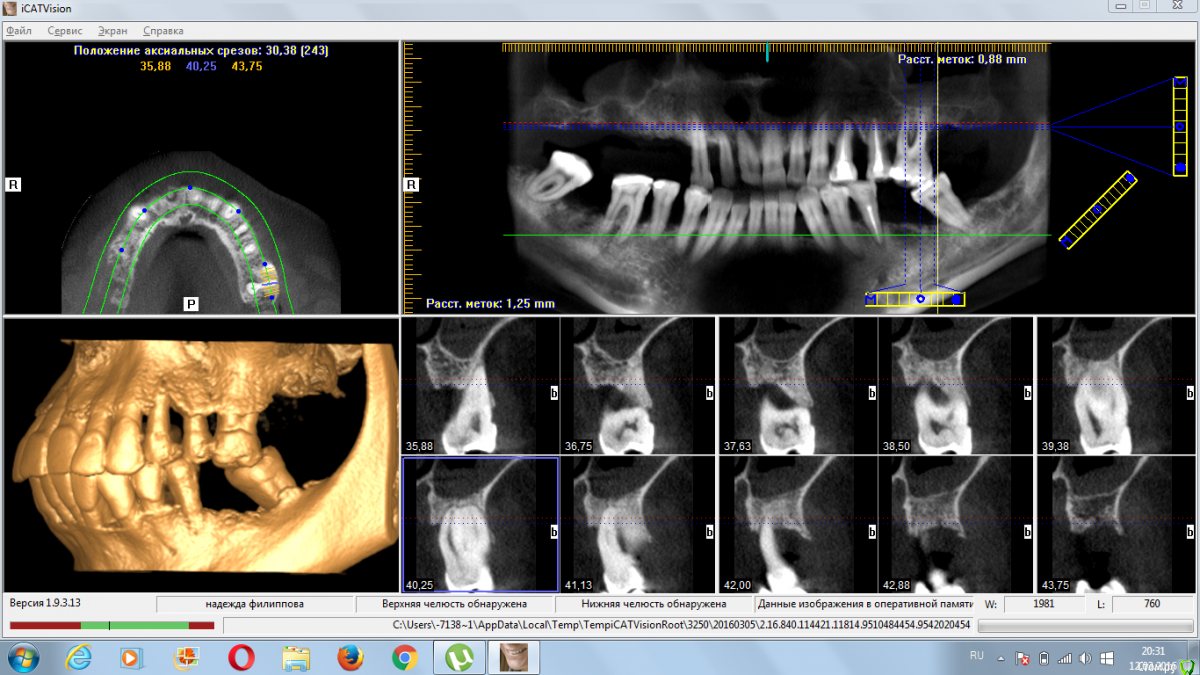

4ebstom Опубликовано 12 марта, 2016 Поделиться Опубликовано 12 марта, 2016 Коллеги,прошу помощи в плане лечения.36 лет,Ж.Не устраивает ЧСПП.Отмечает резкое расшатывание зубов.Соматику отрицает. Предварительно прикинул план лечения:1.Удаление2.Имплантация во всех сегментах.(синусы+нкр)3.Проф.чистка.Собственно вопросы:1.Как быть с утолщением слизистой пазух?Консультация ЛОР?2.Кюретаж открытый или?3.Как быть с протрузией?Ваши замечания и коррективы?Спасибо всем откликнувшимся. Ссылка на комментарий

Доктор Дмитрий Опубликовано 12 марта, 2016 Поделиться Опубликовано 12 марта, 2016 По поводу пазух- надо кт повыше сделать, скорее всего соустья свободные и оперировать можно. Вы сузили показания для удаления,по крайней мере на вч надо все удалять, даже если оставить 2,1 2,2 2,3 под временную опору- это ничего не даст. Импланты можно установить по шаблону. Можно обойтись без синусов, если по другому распланировать хирургию, например- все на 4. 1 Ссылка на комментарий